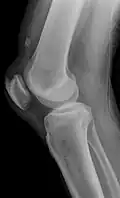

| An x-ray demonstrating quadriceps tendon rupture. Note the abnormal angle of the patella and soft-tissue swelling marked by the arrow. | |